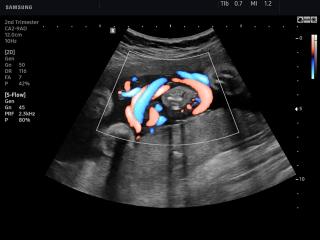

В разделе "Акушерство" атласа представлены результаты ультразвуковых исследований беременных на разных сроках. Здесь вы можете посмотреть изображения внутренних органов, мозга, сердца и пола плода, эхограммы многоплодной беременности, кровотока в плаценте и пуповине, пороков развития и др.